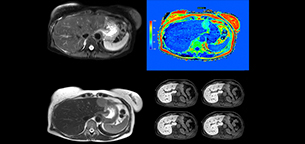

Dr. Kukuk’s liver exam begins with T2-weighted imaging, single shot and with fat suppression. “We always perform diffusion weighted imaging (DWI) with four b-values (0, 50, 250, 800) for lesion characterization, for monitoring after therapies, and for visualization of small lesions. Before giving contrast we routinely use the mDIXON Quant fat quantification sequence. Then we use dynamic e-THRIVE with an in-plane spatial resolution of 1.5 mm and high temporal resolution in just four breathholds of 13.1 seconds.”

“Contrast enhancement is important to help us characterize lesions, for follow up in oncology patients and to inform clinicians when deciding on possible changes in the therapeutic regimen,” Dr. Kukuk explains. “Because we use liver-specific contrast agents we can obtain the T2-weighted images after the dynamic, to bridge the waiting time needed with these contrast agents. Just before the patient leaves the scanner we acquire another e-THRIVE in the axial plane and one or two coronals.”

Robust motion correction and high spatial resolution with MultiVane XD

“Using MultiVane XD motion correction, we are now able to acquire high spatial resolution T2-weighted images without seeing relevant motion,” says Dr. Kukuk. “It’s a great technique to obtain high spatial resolution images of the pancreas or the liver, as well as the surrounding organs and tissues. MultiVane XD can be combined with dS SENSE parallel imaging, allowing us to reduce specific absorption rates (SAR), acquire high spatial resolution in short acquisition times, and at the same time reduce artifacts caused by motion in adjacent tissues and organs.”

“In comparison to single shot T2-weighted TSE, this approach with MultiVane XD motion suppression provides higher spatial resolution. In addition, it is especially valuable in patients who cannot hold their breath or have some disabilities. My impression is that this sequence has the potential to substitute for, or even replace, the T2-weighted single shot sequence in our liver exams, because of good and consistent delineation of small lesions.”

“We have performed a study comparing mDIXON Quant fat percentages with results from histopathology. The correlation with different histologic methods was very good and also the correlation with MR spectroscopy was far above 0.9 – a nearly perfect correlation,” says Dr. Kukuk.

Non-invasive liver fat quantification in a breathhold with mDIXON Quant

“Fatty liver disease is a common condition. Studies found a prevalence of non-alcoholic fatty liver disease in up to 44% in the general European population [1]. Liver fat cannot be quantified by ultrasound or CT, so biopsy has been the way to quantify fatty liver disease so far,” says Dr. Kukuk. “mDIXON Quant now allows non-invasive quantification of liver fat, which is valuable for both diagnosis and follow-up during dietary changes or therapy, for instance in hepatitis C.”

“The mDIXON Quant fat fraction maps provide quantitative information and also anatomical detail. The sequence is fast, usually taking about 16 seconds, which is just a breath hold for most patients. It definitely improves our efficiency.”